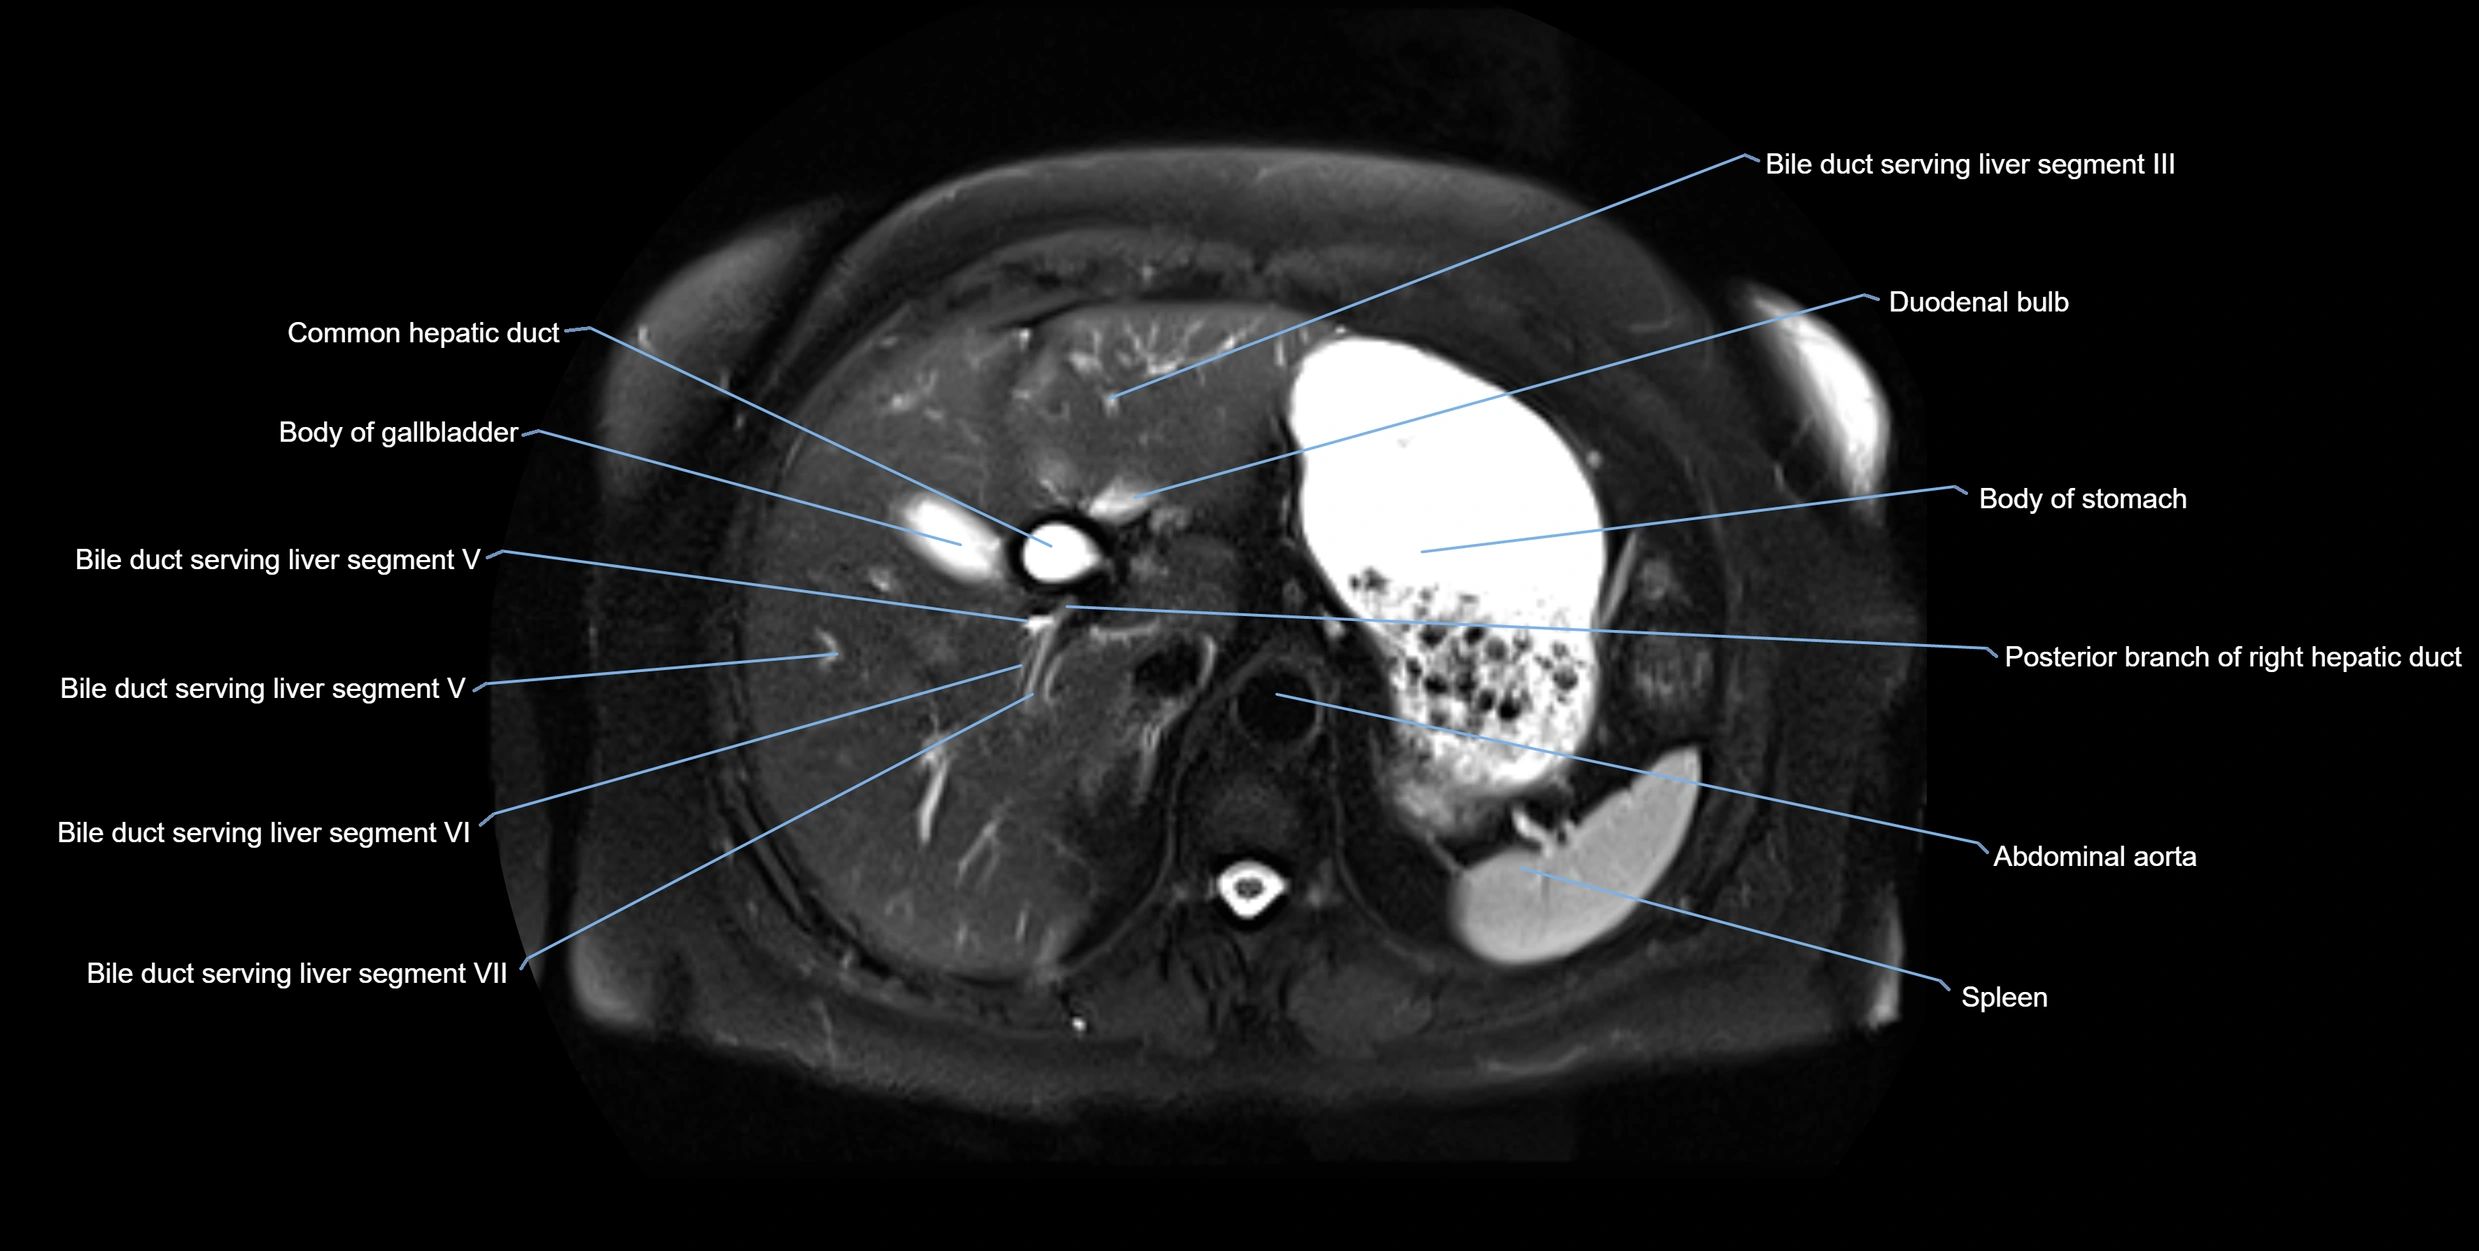

T2-weighted images:

• Duct fluid appears bright

• Accessory duct seen as a fine high-signal tubular structure in pancreatic head

T2 Fat-Saturated HASTE (single-shot):

• Accessory duct: bright, thin linear structure in pancreatic head

• Stones, strictures, or air bubbles appear as dark filling defects

• Excellent for rapid evaluation of duct patency

MRI image

image